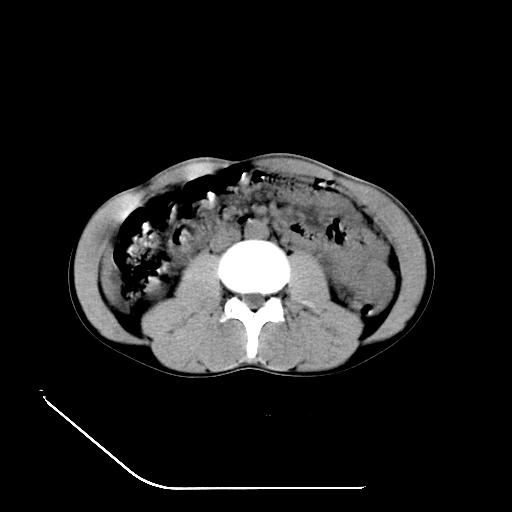

顺便请各位老师认真看看7号片

各位老师觉得胆囊是不是有点积血。我在原始片看胆囊密度不均,似有小液平面

再有就是支持楼主,胆囊7日片比5日片不仅增大许多,靠后下更见液液分层,应该是有积血。

结果收到,谢谢楼主,另外反过来看这个地方是不是游离气体影